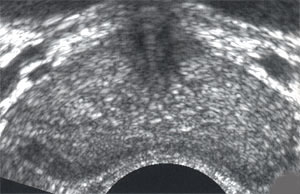

УЗ-исследование per rectum позволяет оценить однородность ткани железы, ее размера, звукопроводность, четкость контуров, состояние венозного парапростатического сплетения.

• изменение эхогенности ткани с наличием гиперэхогенных включений, причем более четко при трансректальном сканировании - 94,6% наблюдений,

• диффузные или очаговые уплотнения ткани железы вследствие фиброзных изменений - 80,5% наблюдений,

• наличие единичных или множественных кальцинатов, сливающихся в конгломераты - 56% наблюдений,